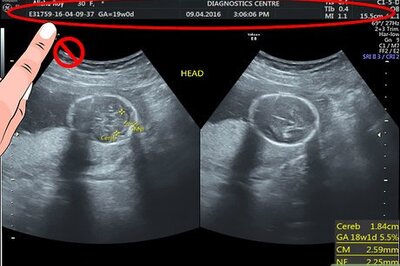

An ultrasound may be performed for a variety of reasons, but looking at a baby in the womb is the most common reason. If you have recently had an ultrasound and you want to know how to interpret the images on your ultrasound, then you may benefit from lea...